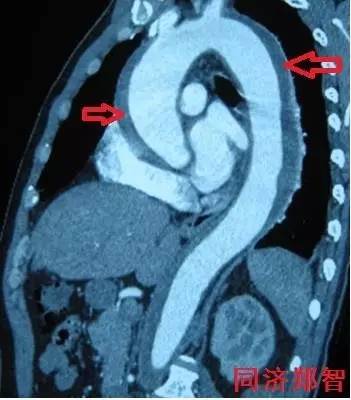

① Stanford B型 主动脉壁间血肿的CTA重建(图1),提示胸降主动脉以远的主动脉壁病变(红箭头所示)。

图1

② Stanford A型 主动脉壁间血肿的CTA重建(图2),提示升主动脉和胸降主动脉的主动脉壁均有病变(红箭头所示)。

图2